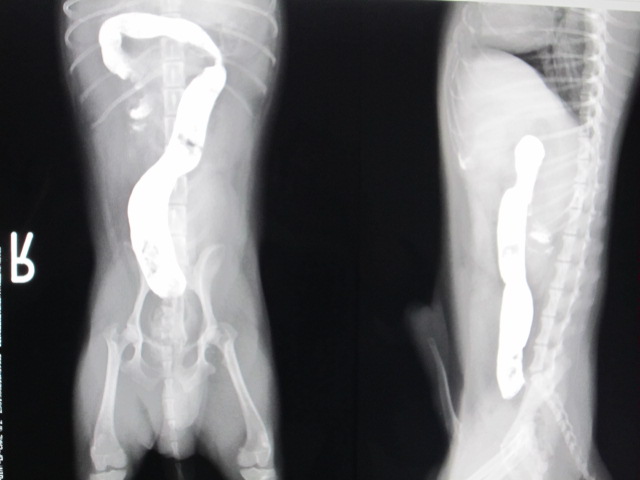

術後

術後のレントゲンです。

バリウムは結腸まで流れました。